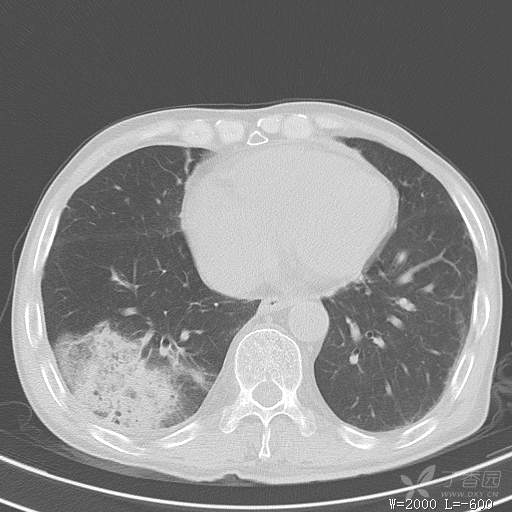

简要病史:主因发热伴腰背部疼痛2小时于2018-06-27,09:30 入院。患者无高血压,冠心病、糖尿病病史,无慢性咳喘史,不吸烟。否认食物药物过敏史。患者于入院前2小时出现发热,体温37.5℃,无咳嗽,咳痰,伴右侧腰背部疼痛,伴呕吐2次,呕吐物为黄绿色胆汁,大便2次,为稀便,无咯血,无胸闷、憋气,无鼻塞、流涕,无尿频、尿急、尿痛,就诊于我院,我院急诊查:上腹部CT:右肾结石,右下肺感染性疾病可考虑,血常规WBC13.54*109/L,GR%45.8%,急诊以“发热待查:肺感染?”收入院。

辅助检查:上腹部CT:右肾结石,右下肺感染性疾病可考虑,血常规:WBC13.54*109/L,GR%45.8%,。心肌酶示:谷草转氨酶12U/L,乳酸脱氢酶328U/L,肌酸激酶20U/L,肌酸激酶同工酶7U/L,α-羟丁酸脱氢酶277U/L,查凝血常规示:凝血酶原时间12.5秒,国际标准化比值1.07,活化部分凝血酶原时间32.6秒,纤维蛋白原浓度1.77g/L,凝血酶时间15.6秒。

临床诊断:1.腰背部疼痛原因待查:1.肺炎?2.泌尿系结石?。

治疗经过:抗感染及止痛对症处理。治疗效果不好,患者腰痛是由什么引起的?